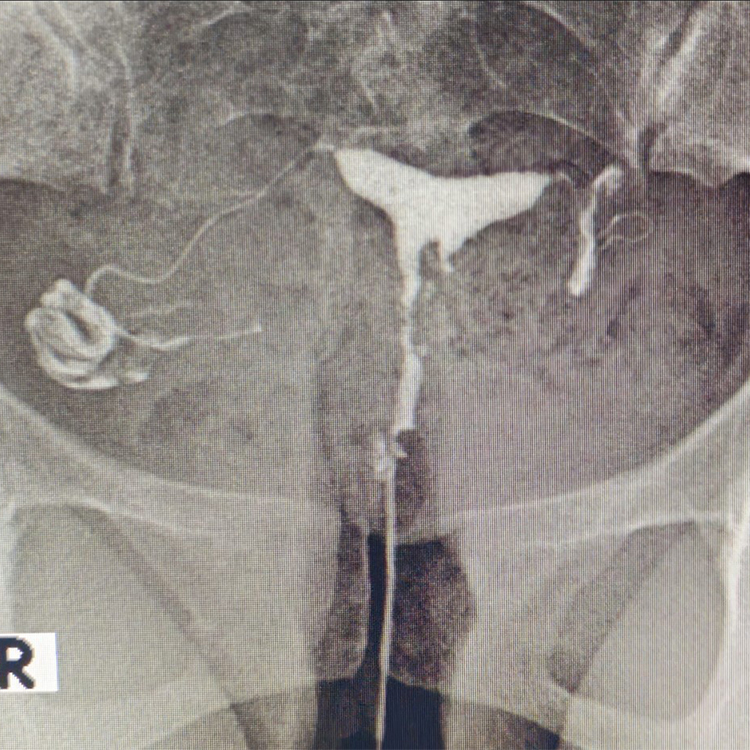

Modern radyolojik görüntüleme, hastalıkların net ve güvenilir şekilde değerlendirilmesini sağlar. Doğru tanı; gereksiz işlemlerin önüne geçer, tedavi sürecini hızlandırır ve hastaya güven verir.